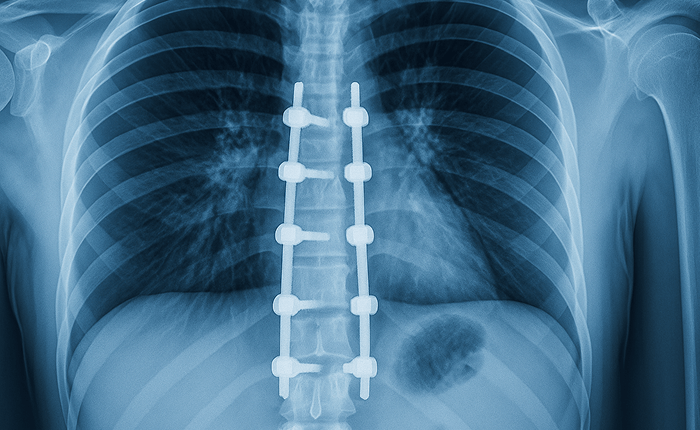

• Hardware related discomfort from screws or rods

Pain that continues after spinal surgery, or returns months later, is more common than most patients expect. It can affect the neck, mid back, or lower back depending on the type and location of surgery. This pain can limit daily activities, sleep, or mobility, and may feel different from the original pain.